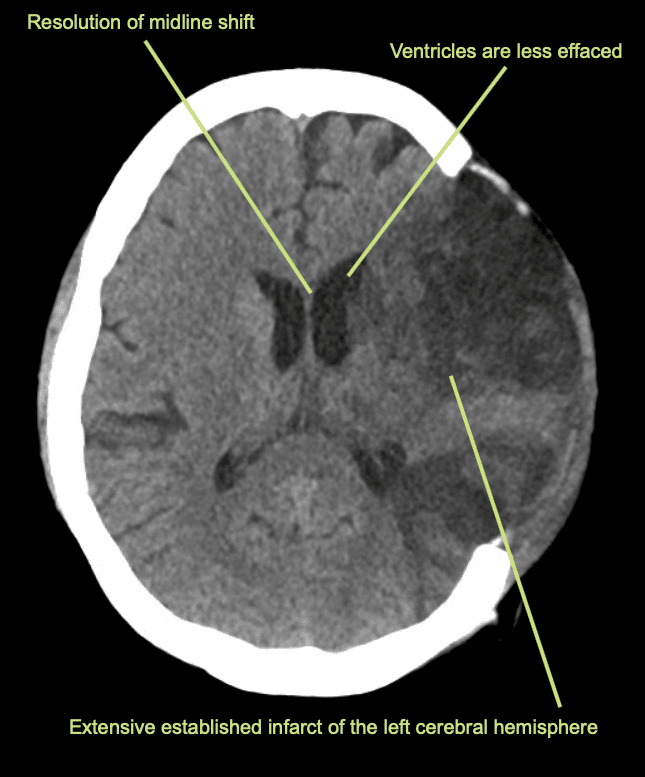

Il giorno successivo viene eseguita una TAC di controllo.

Interpretazione della TAC a 24 ore